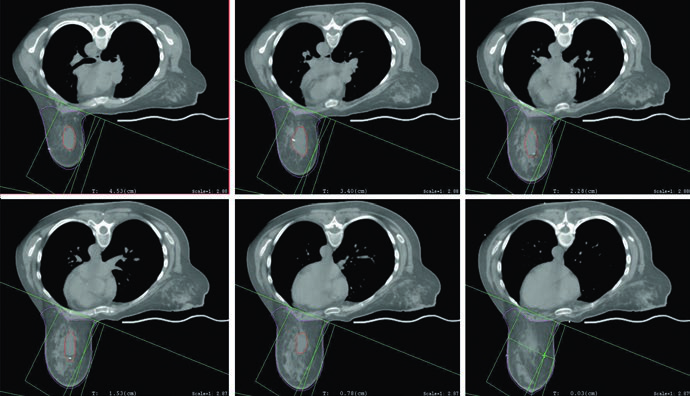

Câncer de Pulmão

Em pulmão, o livro assume sem rodeios que planejamento por tomografia e manejo do movimento respiratório são padrão tanto em NSCLC quanto em SCLC. 3D-CRT, IMRT e SBRT usam múltiplos ângulos e mudam a conformidade de dose, então o contorno correto do alvo, das estruturas normais e dos órgãos de risco passa a ser inseparável da leitura de DVHs e do entendimento das cadeias mediastinais em risco. O artigo dedicado aprofundará o delineamento no câncer de pulmão.

No pâncreas, o texto já entra em técnica. A IMRT aparece como abordagem cada vez mais padrão em cenários neoadjuvante, adjuvante e definitivo; 3D-CRT ainda pode ser útil em paliação e em alguns neoadjuvantes; abordagens ablativas exigem SBRT ou técnicas guiadas por imagem. O capítulo também traz um protocolo concreto de simulação com contraste: 150 cc a 5 cc/s, com fases tardia arterial aos 35 s e portal venosa aos 90 s, detalhe especialmente crítico quando a dose ultrapassa 50 Gy em EQD2. O artigo dedicado explica esse planejamento pancreático em profundidade.